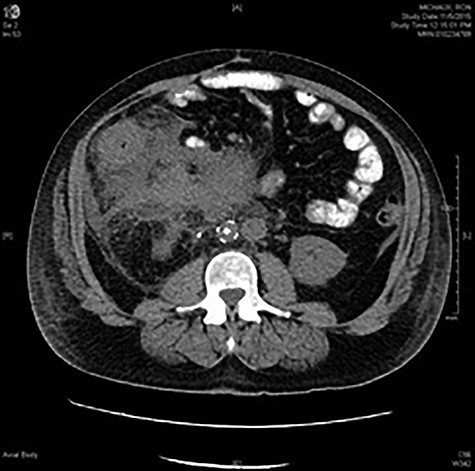

A 53-year-old Caucasian male presented with a 2-week history of abdominal distension, pain, nausea and lethargy. His symptoms began 1 day after an all-terrain vehicle accident during which he suffered blunt-force trauma to his mid-right abdomen. Past medical history was significant for chronic left lower extremity deep vein thrombosis (DVT), managed with warfarin. Initial CT scan demonstrated abnormal thickening of the ascending colon and terminal ileum with surrounding inflammation within the retroperitoneum and colonic mesentery without perforation or abscess (Fig. 1). Further workup included a colonoscopy that revealed a portion of the ascending colon and cecum with edematous and erythematous mucosa. Biopsies showed unremarkable colonic mucosa with benign lymphoid aggregates. The patient was diagnosed with a likely hematoma of the right abdomen and was treated with nasogastric decompression and bowel rest. Given symptomatic improvement and belief that findings were secondary to trauma, conservative management was continued and the patient was discharged home in good condition. However, the patient was readmitted with recurrence of abdominal distention, pain and new-onset emesis. The patient continued to have bowel movements and pass flatus; however, physical exam was remarkable for worsening right-sided abdominal distention and rigidity. Repeat CT scan demonstrated no interval improvement in imaging findings and the decision was made for operative intervention due to increasing severity of symptoms, inability to tolerate oral intake and concerns for bowel obstruction.

CT abdomen and pelvis with oral contrast at the level of L2 showing marked inflammatory changes surrounding the ascending colon and obscuring the colonic margins. Phlegmonous changes are seen extending to the root of the mesentery, in the left perinephric space and inferiorly into the pelvis. Infrarenal IVC filter and right ureteral stent are in place.